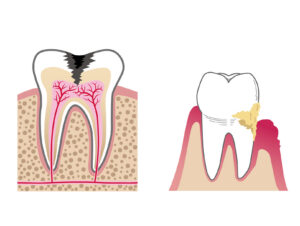

歯周病とは?(原因、症状、治し方、治療法など)

歯周病と歯並びの関係(矯正治療の必要性)

頑張って歯を残す or 抜いてインプラントにする

歯根端切除術(根管治療で治らない根尖病変の治療法)